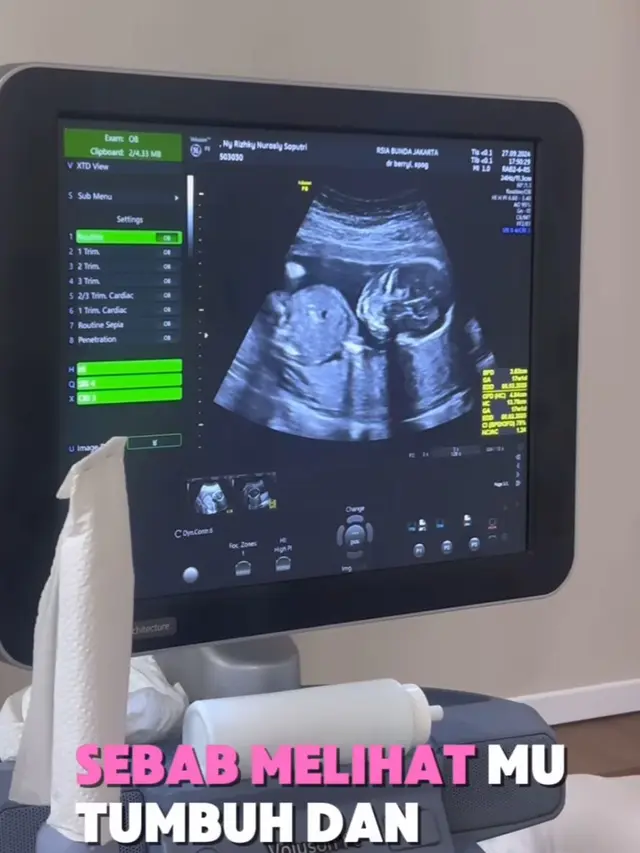

Setelah melalui masa sulit, Kiky Saputri membagikan kabar bahagia pada tanggal 29 Juni 2024, bahwa ia kembali diberi kesempatan oleh Tuhan untuk mengandung.

Dalam video yang diunggah di Instagram, Kiky terlihat penuh haru saat mengumumkan kehamilan keduanya, disertai dengan doa dan harapan besar agar kehamilan ini berjalan lancar hingga kelahiran.

Pada tanggal 4 Oktober 2024, Kiky secara resmi mengumumkan kehamilannya melalui Instagram. Dalam unggahan tersebut, Kiky menuliskan, "Bismillah... Alhamdulillah... Terima kasih untuk semua doa baik. Kami juga mendoakan, semoga yang belum... akan disegerakan."

Dengan baby bump yang sudah terlihat besar, Kiky berharap kehamilan ini akan berjalan lancar hingga ia dan suaminya dapat bertemu dengan buah hati yang dinantikan.